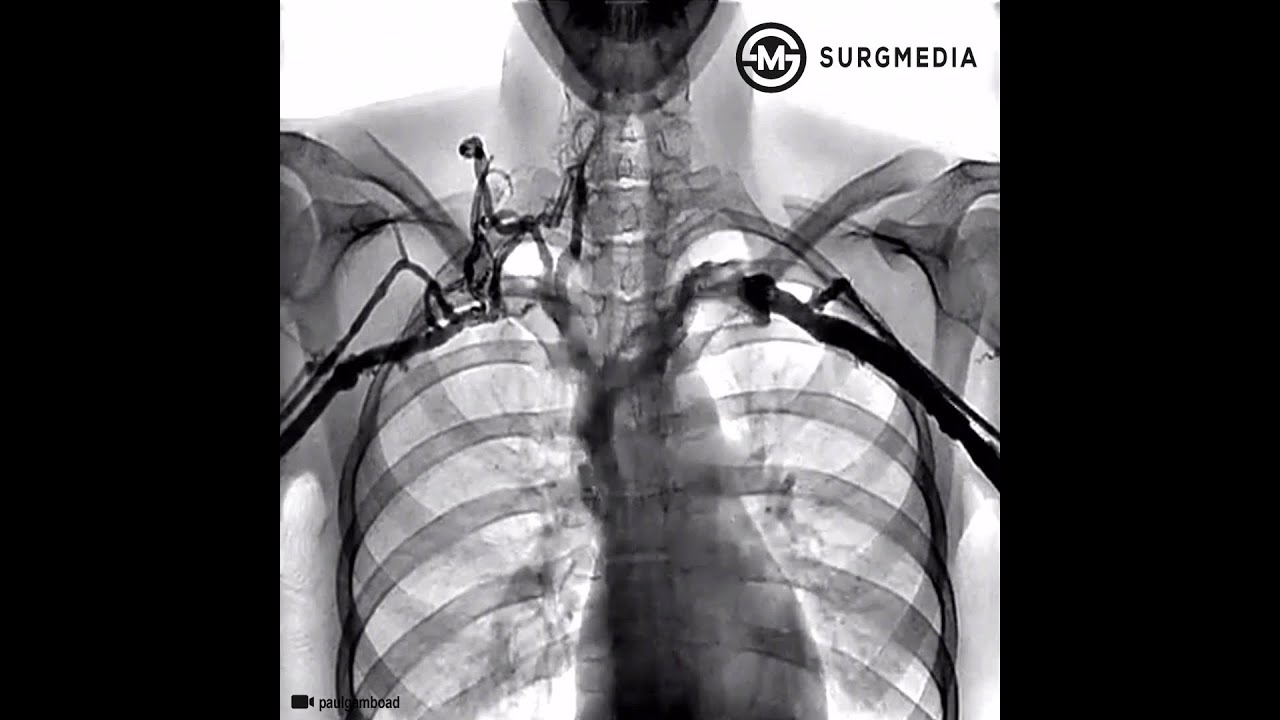

Here is 2021 Catheter Angiogram showing the compression as well